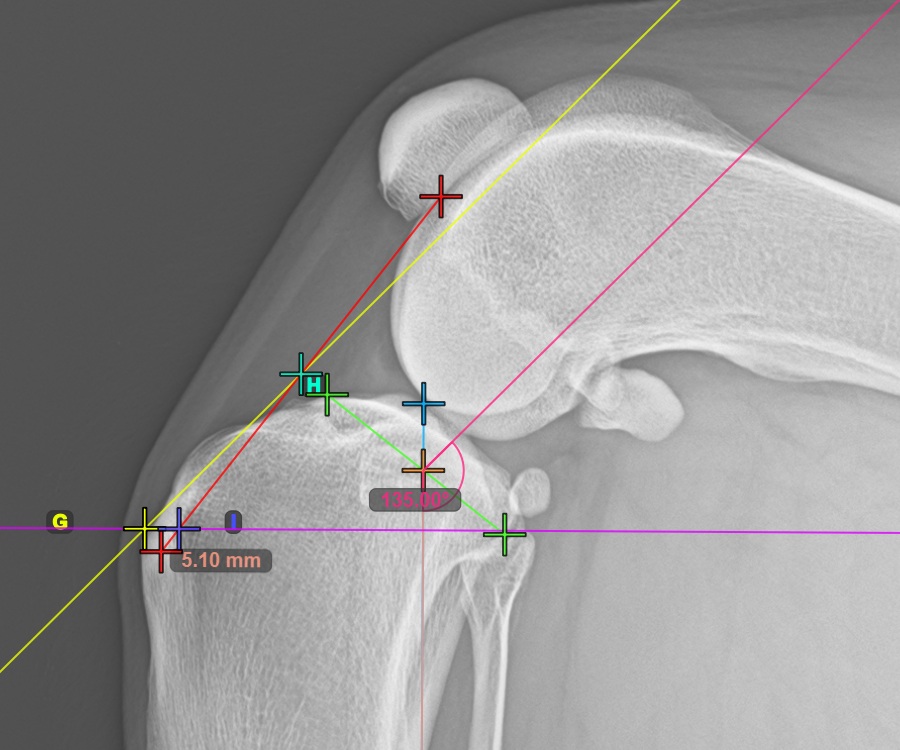

Um die TTA Rapid-Variante des TTA-Messverfahrens abzuschließen, markieren Sie den hintersten Punkt der Crista Tibiae (Tuberositas Tibiae). Der Abstand zwischen der Tuberositas Tibiae und den automatischen TTA Rapid-Hilfslinien ist die erforderliche Anpassung für das TTA-Verfahren.

Das Bild unten zeigt die übliche Platzierung der Tibiatuberositas, des markantesten Punkts des Tibiakamms.